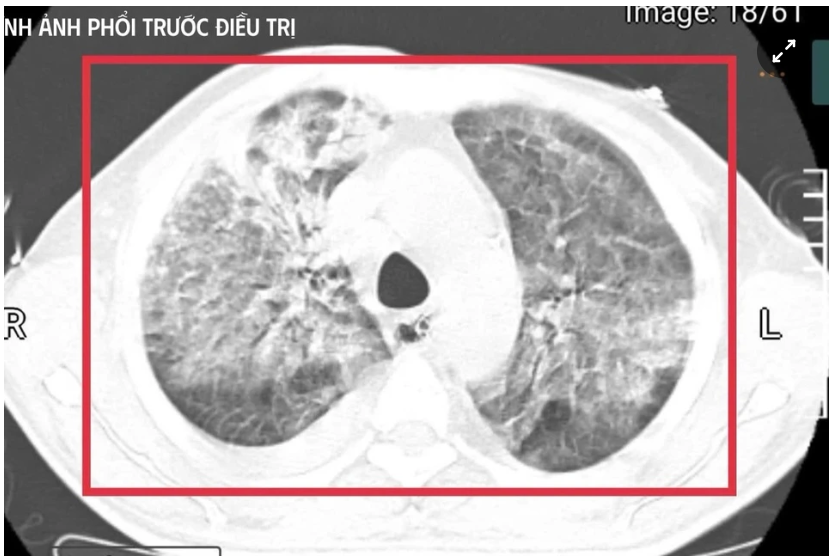

Bệnh nhân được xác định nhiễm Burkholderia pseudomallei - tác nhân gây bệnh Whitmore. Ảnh: BVCC.

Bệnh nhân nam L.V.T. (35 tuổi, quê Nghệ An) sinh sống và làm việc tại Thái Lan - khu vực lưu hành bệnh Whitmore cao. Anh có tiền sử đái tháo đường mới phát hiện. Khoảng 5 tuần trước khi về Việt Nam, người đàn ông xuất hiện sốt cao liên tục, khó thở, kích thích nhiều, phải nhập cấp cứu tại một cơ sở y tế ở Thái Lan.

Tại đây, bệnh nhân được đặt nội khí quản thở máy; kết quả cấy máu xác định nhiễm Burkholderia pseudomallei - tác nhân gây bệnh Whitmore. Dù được điều trị ban đầu, tình trạng vẫn diễn tiến nặng nên gia đình xin chuyển về Việt Nam để tiếp tục điều trị. Nhưng chỉ sau ít ngày, người đàn ông này rơi vào sốc nhiễm khuẩn, suy đa tạng, sốt cao liên tục, rối loạn ý thức và được chuyển gấp ra khoa Cấp cứu, Bệnh viện Bệnh Nhiệt đới Trung ương (Hà Nội).